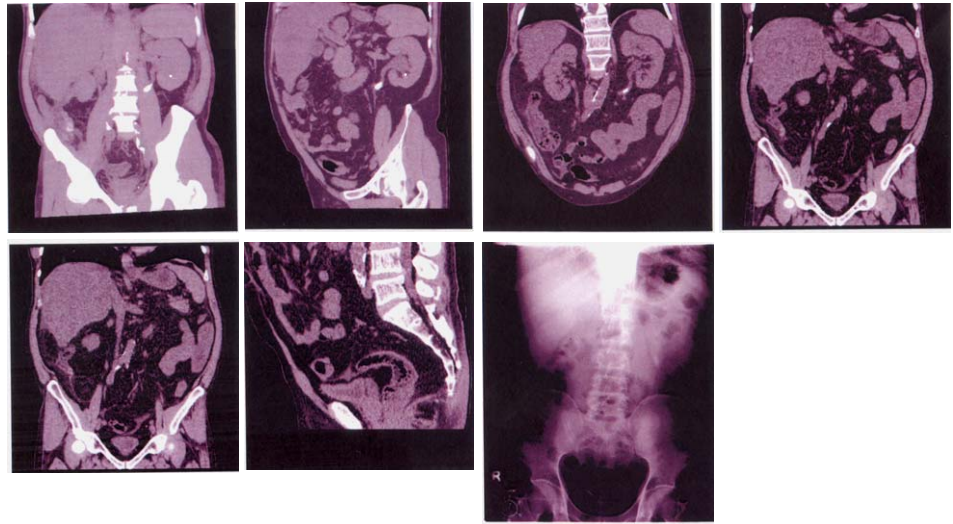

65 52 歲的男性病患,長期酗酒及患有慢性肝炎,長期在肝膽內科追蹤。最近作腹部超音波發現腎盂積 水,故轉至泌尿科門診檢查,尿液分析 RBC: 5-10/HPF,WBC: 25-50/HPF,AC sugar: 147 mg/dL, BUN: 78 mg/dL,Cr: 2.3 mg/dL,SGOT: 56 U/L,SGPT: 37 U/L,經 KUB 及 spiral CT without enhanced (電腦斷層攝影)(如圖),可能的診斷是:

(A)左側輸尿管結石,左腎結石 (B)僅左輸尿管結石 (C)兩側輸尿管結石,左腎結石 (D)右側輸尿管結石,右腎結石